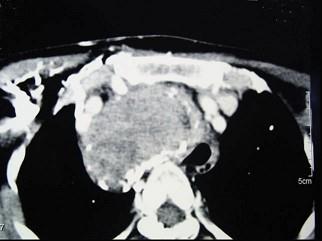

问题 女性,48岁,颈部包块3年,近来胸闷、憋气、胸痛,CT扫描如图,请选择正确的描述和答案 ( )

选项 A、胸骨后甲状腺肿是指甲状腺50%位于胸骨后 B、胸骨后甲状腺肿是指甲状腺60%位于胸骨后 C、考虑为血管瘤 D、考虑为双侧甲状腺肿大 E、考虑为胸骨后甲状腺肿

答案 AE